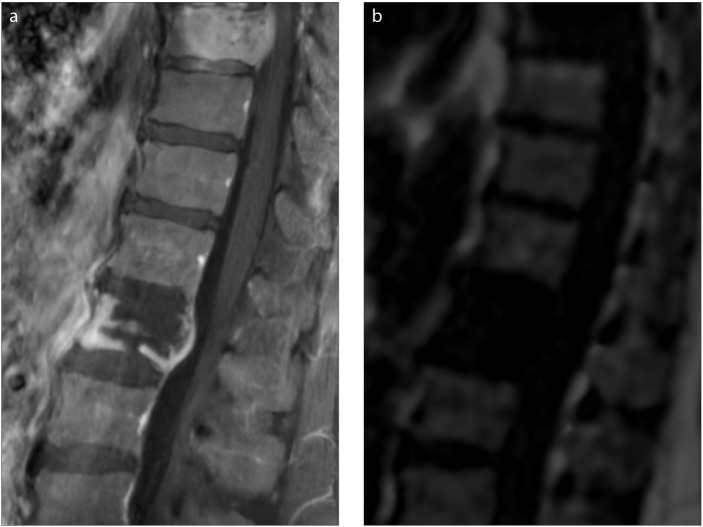

Magnetic resonance imaging-proton density fat fraction (MRI-PDFF) is an emerging quantitative imaging biomarker that accurately measures the fat fraction of tissue by correcting factors influencing magnetic resonance signal intensity. Beyond fat quantification, it also measures R2* which is a direct measure of iron concentration. The utilization of MRI-PDFF in liver diseases is well established. In the present review, we focused on applications of MRI-PDFF in different body areas including pancreas, bone, muscle, spleen, testis, visceral, and subcutaneous adipose tissue. Future studies can enable tracking of quantitative fat fraction changes in different organs simultaneously, which can be critical in understanding fat metabolism.